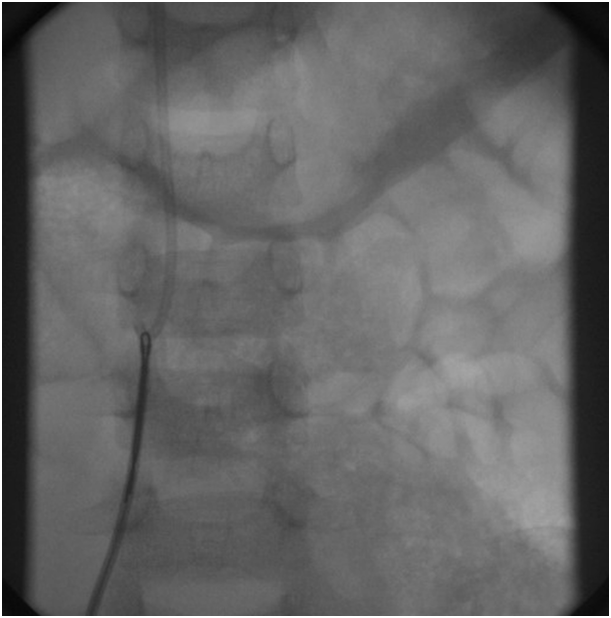

The child was electively intubated and ventilated with general anesthesia. Initial attempts at snaring the Port-A-Cath through the right internal jugular vein were not successful (Figure 4). Therefore, the heart was accessed through the right femoral vein with 6F pediatric introducer sheath. Then 6F CORDIS MPA2 catheter was used to cross to the right ventricle outflow tract where the tip of the Port-A-Cath was located (Figure 5).

Figure 4 Shows the migrated Port-A-Cath as well as an internal jugular vein catheter.

Figure 5 Locating the tip of the Port-A-Cath through the right ventricle outflow tract.